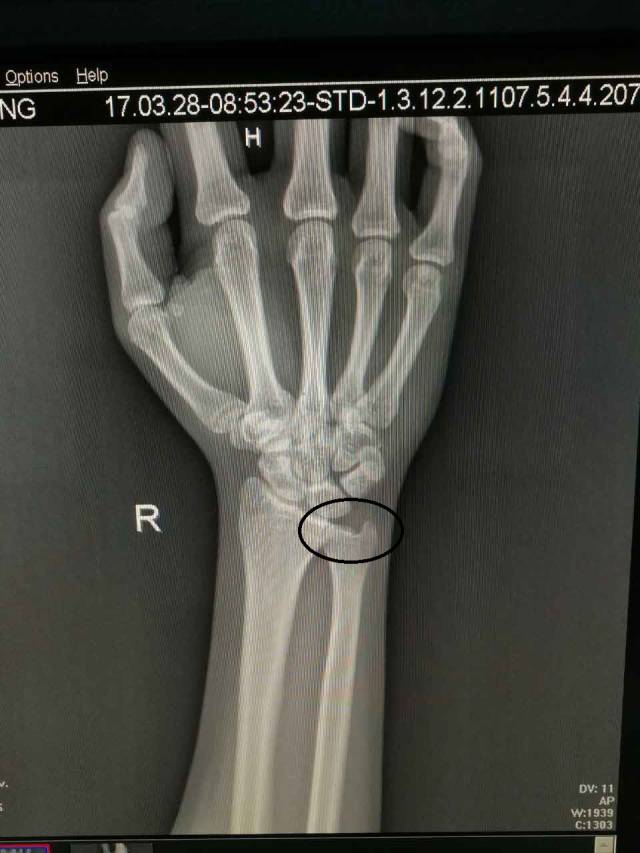

(图中所打圈的位置就是下尺桡关节)

针对没有经验的人来说,很多人会以为损伤是撞到“麻经”了,丝毫没有觉察,其实已经下尺桡关节脱位了。其实下尺桡关节脱位的伤害不亚于骨折,如何自测有没有下尺桡关节脱位呢,笔者告诉大家一定要关注以下4点: